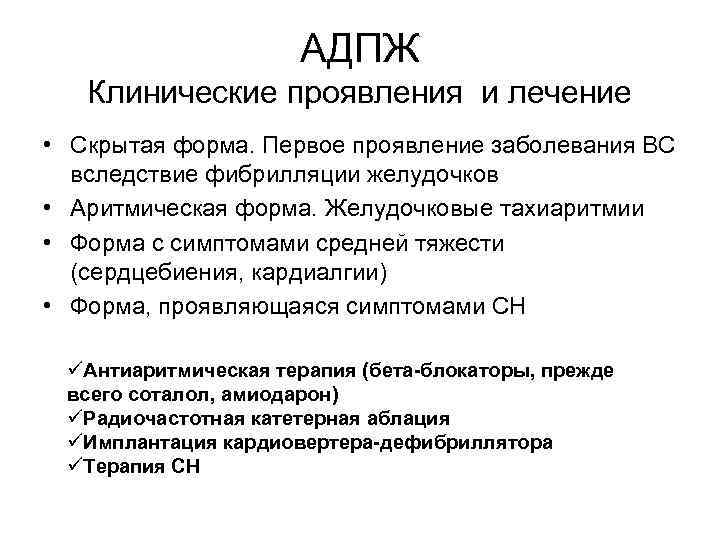

АДПЖ Клинические проявления и лечение • Скрытая форма. Первое проявление заболевания ВС вследствие фибрилляции желудочков • Аритмическая форма. Желудочковые тахиаритмии • Форма с симптомами средней тяжести (сердцебиения, кардиалгии) • Форма, проявляющаяся симптомами СН üАнтиаритмическая терапия (бета-блокаторы, прежде всего соталол, амиодарон) üРадиочастотная катетерная аблация üИмплантация кардиовертера-дефибриллятора üТерапия СН

АДПЖ Клинические проявления и лечение • Скрытая форма. Первое проявление заболевания ВС вследствие фибрилляции желудочков • Аритмическая форма. Желудочковые тахиаритмии • Форма с симптомами средней тяжести (сердцебиения, кардиалгии) • Форма, проявляющаяся симптомами СН üАнтиаритмическая терапия (бета-блокаторы, прежде всего соталол, амиодарон) üРадиочастотная катетерная аблация üИмплантация кардиовертера-дефибриллятора üТерапия СН